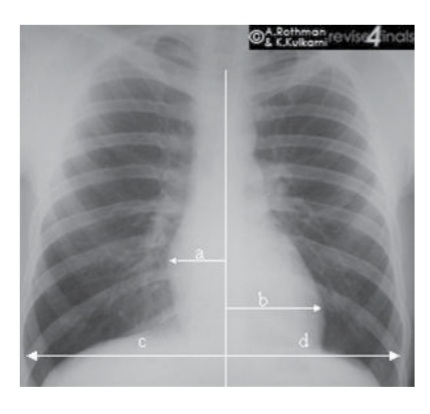

6. CTR (Cardio Thoracic Ratio)

rumus CTR = (a+b)/(c+d)

nilai normal CTR <= 50%